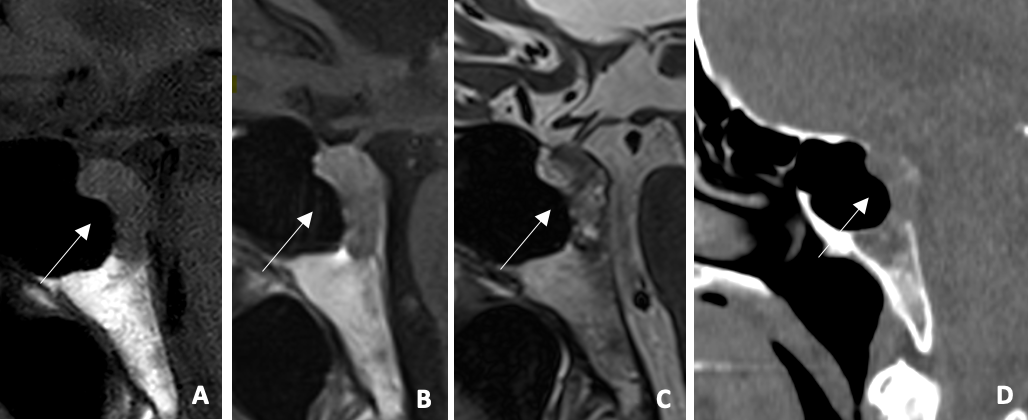

Figure 2

(A) Sagittal T1WI: hypointense expansive clival lesion (B) Sagittal post‑contrast T1WI: mild enhancement (C) Sagittal T2WI: heterogeneous lesion with hyperintense areas (D) Sagittal CT: Lytic clival lesion. Mildy enhancing clival lesion on MRI and lytic on CT.